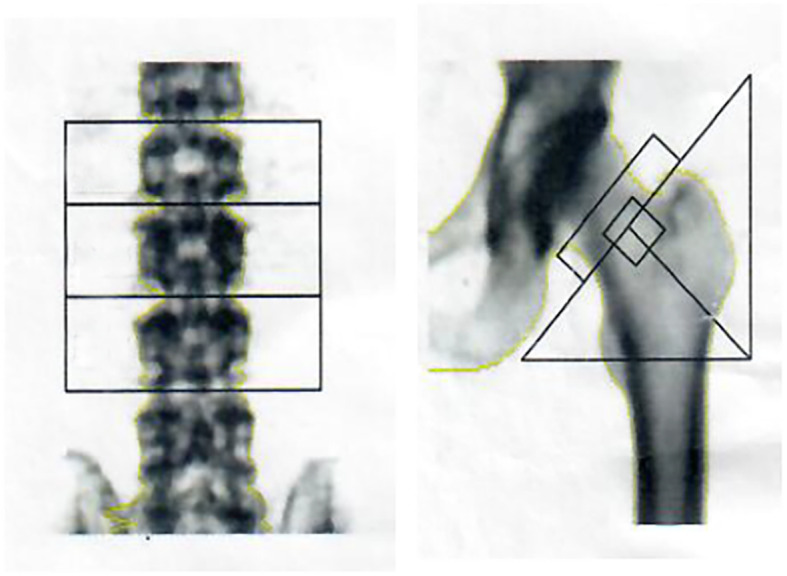

After surgery, the patient’s bone pain remained and aggravated progressively, and renal function was still poor. Urine and creatinine clearance levels were found to be 9.74 mmol/L (3.2–8.2 mmol/L) and 180.5 μmol/L (53–97 μmol/L), respectively. Because bone marrow aspiration results were negative in 2014, bone marrow biopsy and bone mineral density (BMD) were performed again in 2016 in order to exclude the possibility of bone tumor deterioration. The results of the 2016 bone marrow aspiration showed that the bone marrow was approximately normal: the proliferation of granulocytes was erratic; the proportion and morphology of cells in promyelocytes and the following stages were almost normal; erythrocyte proliferation was active, mainly in the middle and late stages of erythrocyte proliferation, and there was no obvious abnormality in morphology; lymphocytes accounted for 33% of the total blood count, and their morphology was normal; megakaryocytes were also normal. In addition, dual-energy X-ray absorptiometry showed a decreased lumbar spine BMD of 0.817 g/cm2 (T-score, − 2.4) and a total BMD of 0.729 g/cm2 (T-score, − 2.0) (T T-score < − 2.5, normal > 1.0). The BMD test results are shown in Fig. 1 and Table 2.

Fig. 1.

BMD test results in 2016